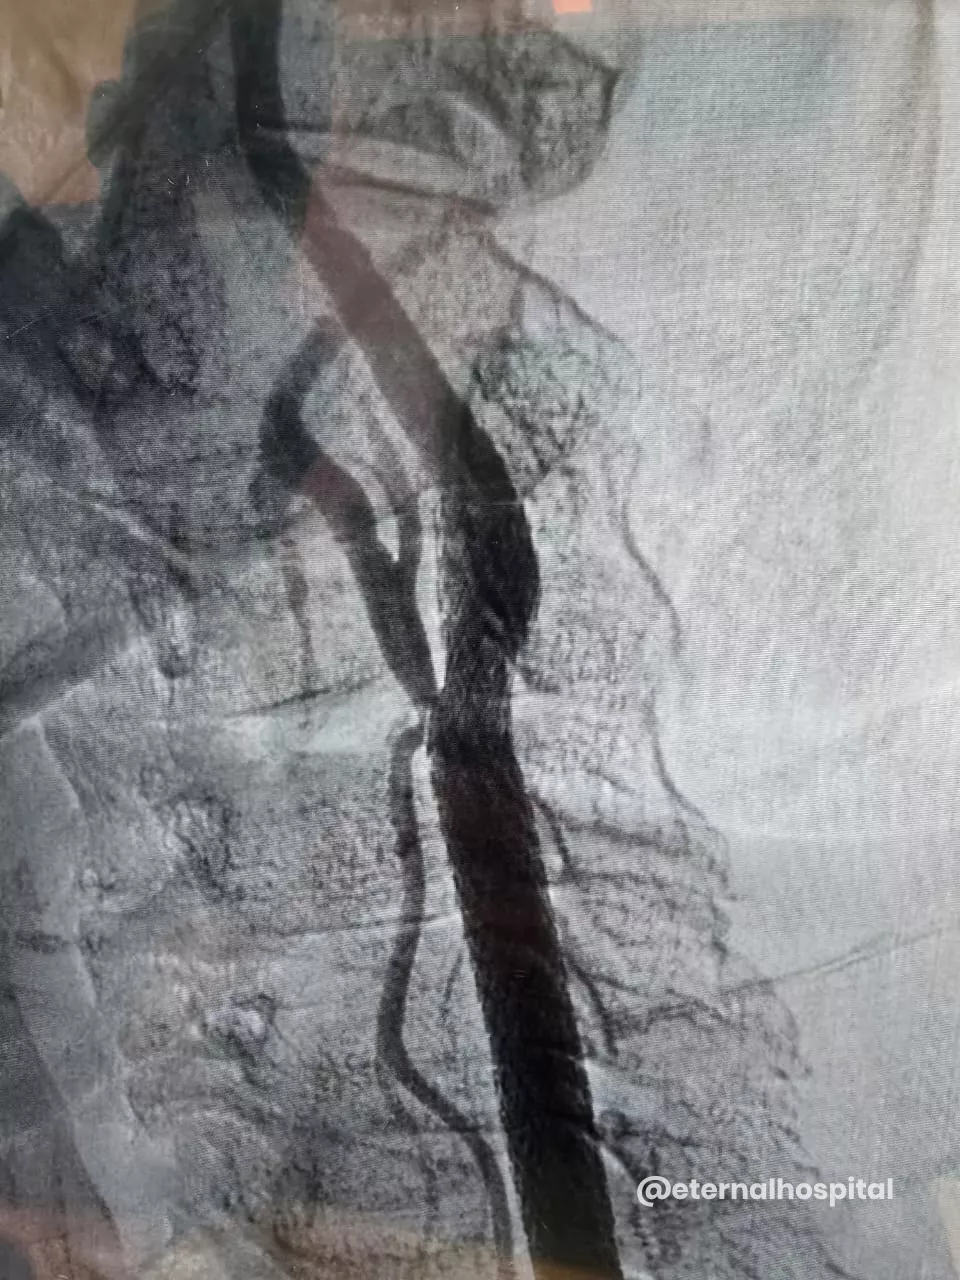

- The doctor numbs the insertion area, makes a small cut to the designated area, and inserts a thin tube (known as a catheter) into the artery.

- With the help of X-ray images, the thin tube is moved up to the narrowed section of the carotid artery.

- A tiny filter could be used to catch any loose debris.

- A small inflated balloon is used to expand the artery, and then the stent is fitted to keep the artery open.

- Afterward, the balloon and filter are taken out.